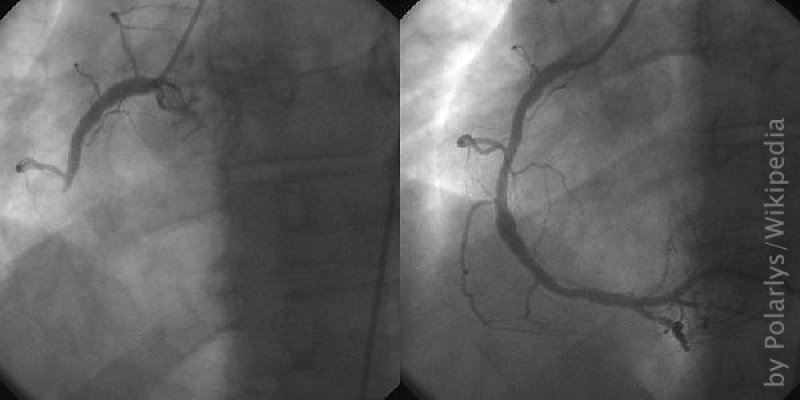

Coronary catheterization- a minimally invasive procedure to access the coronary circulation and blood filled chambers of the heart using a catheter

(c) Polarlys, Wikipedia

Before flying back to Germany, a coronary catheterization is arranged. With this procedure, a narrowing of the blood vessels can be determined and sometimes revised right away. Right after the procedure, it is clear that a stent, an inner vascular support, needs to be placed in an operation. Without an operation, the flight back would be fatal because of the low cabin pressure in the plane. The operation can even be done directly in the hospital. In the meantime, the medical reports are sent to aqua med and evaluated by the aqua med doctors – cooperation is smooth and without complications.

The operation is done while Stefan is fully conscious. The plan was to put one stent in and be done with the operation after half an hour ", Stefan remembers. But during the operation the doctors tell Stefan that he needs four more stents. " I could watch the whole operation on a screen. I could see that some of the arteries in my heart had collapsed, which was pretty disturbing, " says Stefan. Now, there are stents in place of the collapsed arteries.